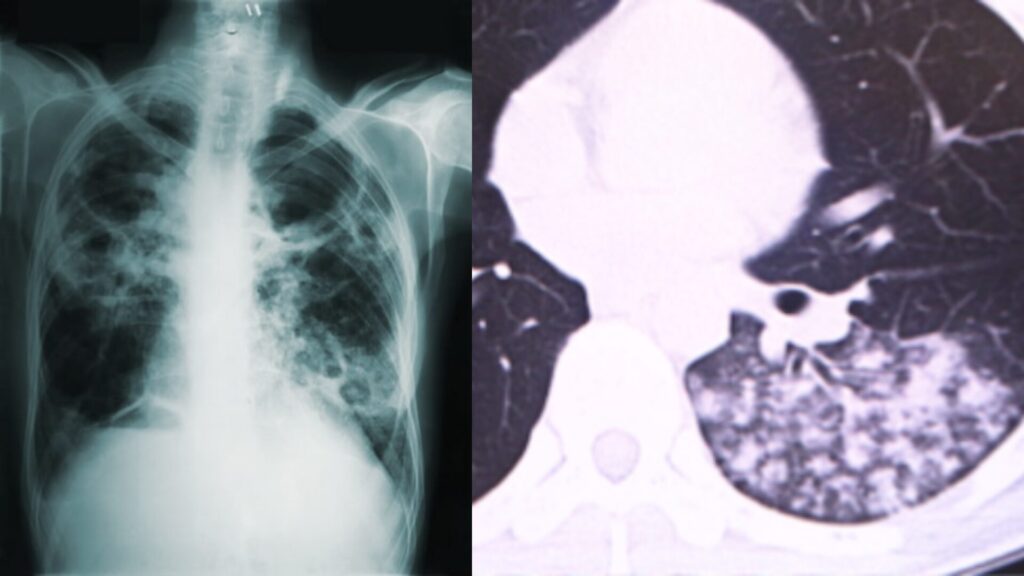

画像でわかる酸素不足・心肺機能の低下

生物は肺で血液中の二酸化炭素と待機中から取り込んだ酸素を交換することで、常に全身に新鮮な酸素を取り込んでいます。

ですが、上記画像のような肺では十分に酸素と二酸化炭素の交換が行われないため、健常者と同じ環境では酸素の摂取が不十分になってしまいます。

画像引用:https://www.shiranaga.jp/heart/

犬も人と同じように肺で酸素を吸収するため、肺が白く濁っている場合は同様に空気の交換がうまくできません。

この変化は画像で明確に確認できるため酸素不足の恐ろしさを視覚的に実感できます。

呼吸状態の悪い患者の撮影画像を見るたびに、早期に酸素環境を整える重要性を強く感じますね。